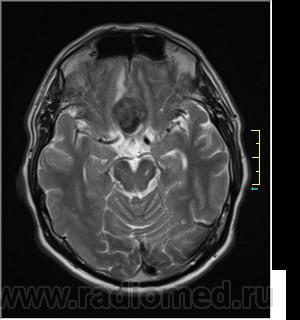

Пациентка направлена на исследование с диагнозом "Гипертонический криз", энцефалопатия неуточненная.

Ax T2:

частично функционирующая аневризма

Иначе говоря, аневризма с хронической геморрагией, т.к. мы видим фракции крови различного возраста.

По-моему, аневризма с пристеночными тромбами.

Постепенное пристеночное образование тромбов приводит к появлению типичного для аневризмы феномена -слоистости МР сигнала в полости аневризмы. Данная картина демонстрирует слоистый характер тромботических масс в полости аневризмы .Функционрирующая часть имеет низкий сигнал во всех режимах сканирования. Дополнительно-перифокальный отек.

А может более корректно интерпретировать как частично тромбированная аневризма... Уж коь речь идет о фракциях, ну то есть о тромбе по сути.... Ну и плюс перфокальный отек головного мозга (вероятнее цитотоксический+вазогенный).